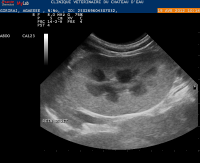

• Suivi de reproduction (gestation)

Les vétérinaires ont recours à l'échographie dans de nombreuses situations ou pathologies.

Grâce à des ultrasons, il est possible de

visualiser les organes internes de

votre animal de compagnie.